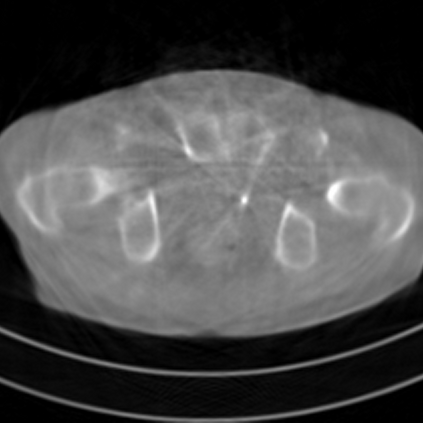

Sparse-view computed tomography (CT) -- using a small number of projections for tomographic reconstruction -- enables much lower radiation dose to patients and accelerated data acquisition. The reconstructed images, however, suffer from strong artifacts, greatly limiting their diagnostic value. Current trends for sparse-view CT turn to the raw data for better information recovery. The resultant dual-domain methods, nonetheless, suffer from secondary artifacts, especially in ultra-sparse view scenarios, and their generalization to other scanners/protocols is greatly limited. A crucial question arises: have the image post-processing methods reached the limit? Our answer is not yet. In this paper, we stick to image post-processing methods due to great flexibility and propose global representation (GloRe) distillation framework for sparse-view CT, termed GloReDi. First, we propose to learn GloRe with Fourier convolution, so each element in GloRe has an image-wide receptive field. Second, unlike methods that only use the full-view images for supervision, we propose to distill GloRe from intermediate-view reconstructed images that are readily available but not explored in previous literature. The success of GloRe distillation is attributed to two key components: representation directional distillation to align the GloRe directions, and band-pass-specific contrastive distillation to gain clinically important details. Extensive experiments demonstrate the superiority of the proposed GloReDi over the state-of-the-art methods, including dual-domain ones. The source code is available at https://github.com/longzilicart/GloReDi.